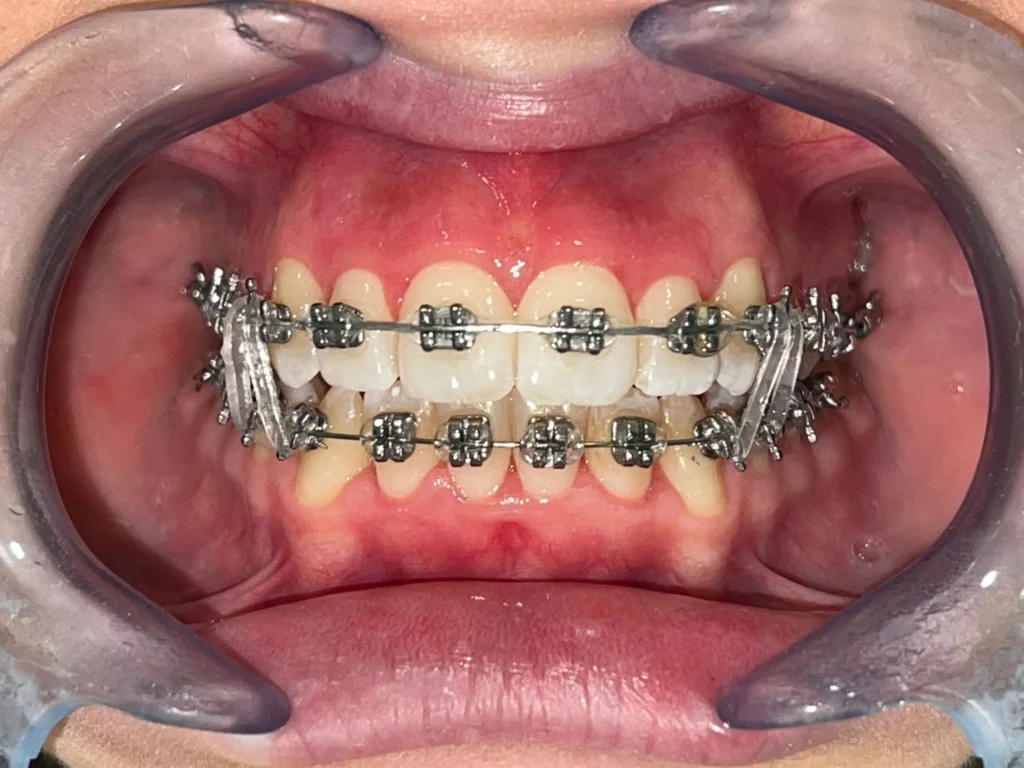

Inoltre, l’apparecchio fisso offre una precisione maggiore nel movimento dei denti, poiché ogni bracket (la placchetta fissata sui denti) è connesso al filo metallico che esercita una pressione costante, facendo sì che i denti si spostino nella direzione desiderata.

Negli ultimi anni, l’ortodonzia ha fatto passi da gigante anche dal punto di vista estetico. Oggi, gli apparecchi fissi non sono più solo in metallo. Esistono infatti apparecchi fissi trasparenti, come quelli in ceramica o zaffiro, che offrono un’estetica migliore rispetto agli apparecchi tradizionali. Questi apparecchi sono progettati per mimetizzarsi con il colore dei denti, rendendo i bracket quasi invisibili e ideali per chi desidera un trattamento discreto. Se non si vuole rinunciare a un apparecchio fisso, queste opzioni estetiche sono perfette per mantenere un aspetto più naturale durante il trattamento.